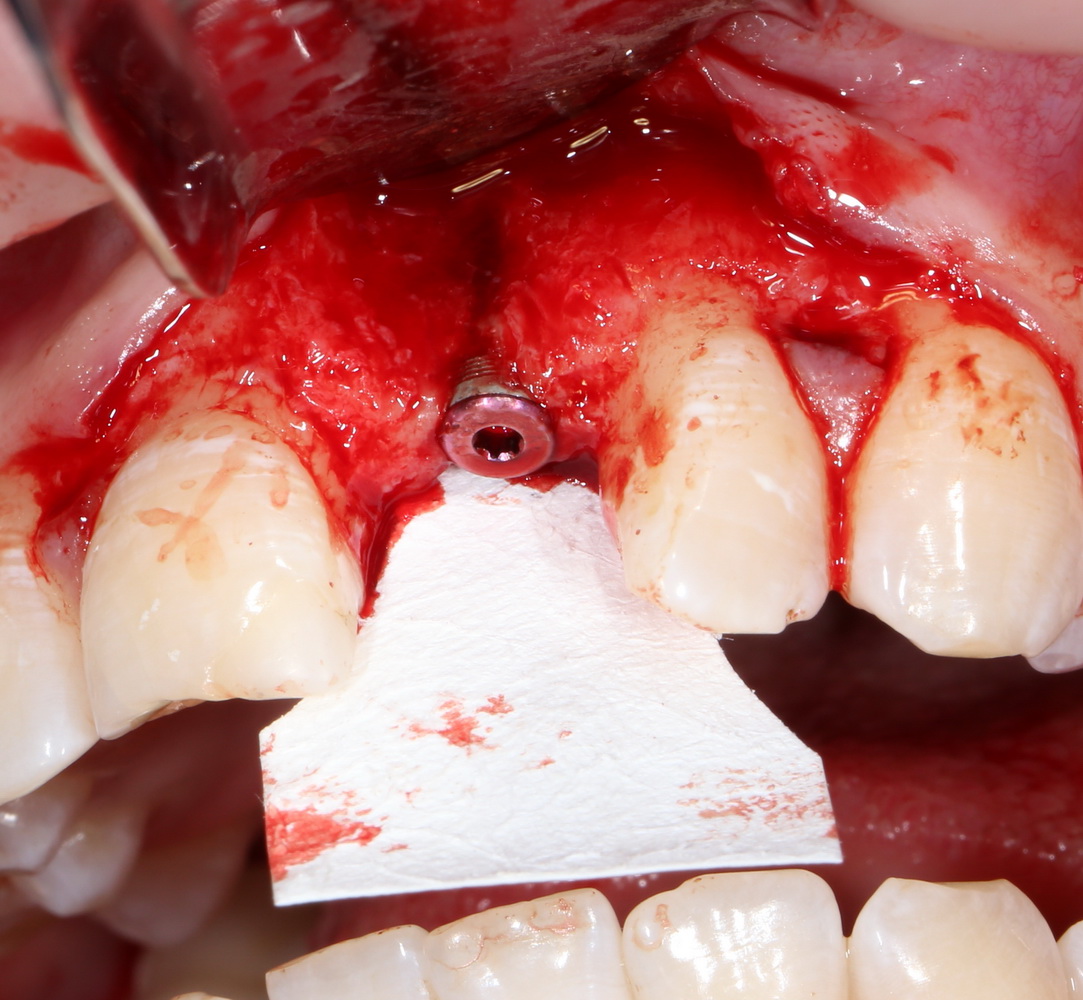

Другой вариант. Имплантируем, но существующего объема костной ткани недостаточно для получения адекватного эстетического и функционального результата:

Поэтому мы используем мембрану Geistlich BioGide и всё ту же аутокостную стружку:

Вот чем мне нравится мембрана BioGide — так это своими свойствами. Предсказуема до мелочей.

Во влажном состоянии она эластична и податлива, поэтому нет необходимости использовать пины или винты: